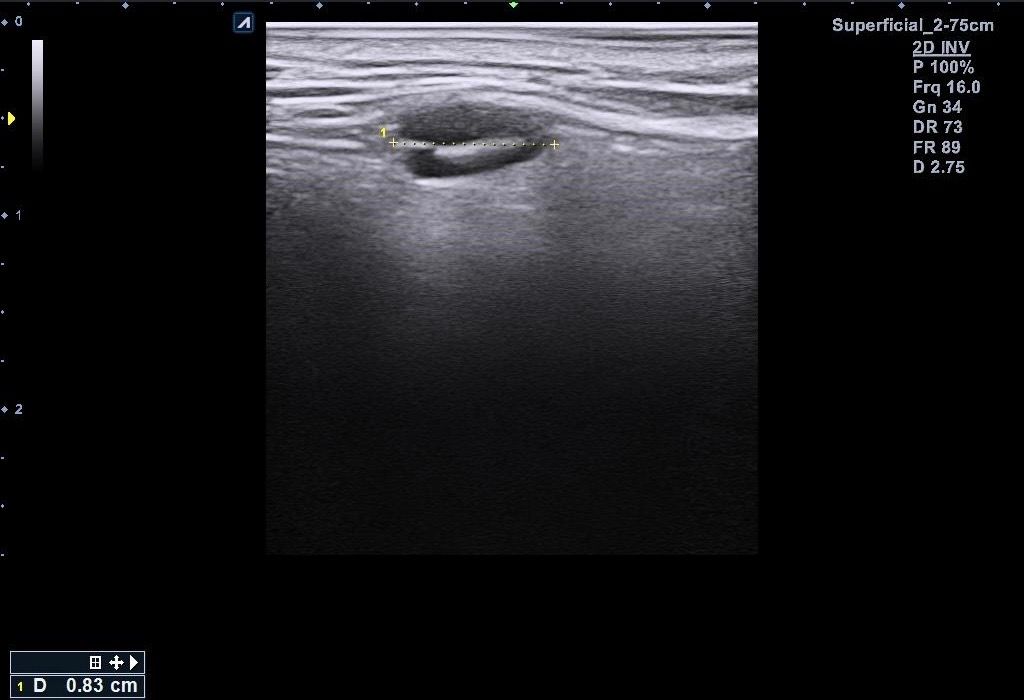

근데 병원에서 지방종이 아니라 임파선 같다고 일단 초음파 본다고 하시고 초음파를 봤는데 의사선생님이 귀 옆에 있는 임파선은 괜찮은데 아래에 있는 임파선이 초음파로 볼때 모양이랑 뭐가 조금 이상하다고 하시면서 대학병원가보라고 소견서를 써주셨습니다 (소견서랑 초음파사진 첨부할게요) 설명들을때 기억상으로는 1 2번째 초음파사진이 귀 아래였던 거 같아요

• 1번 째 사진

• 2번 째 사진